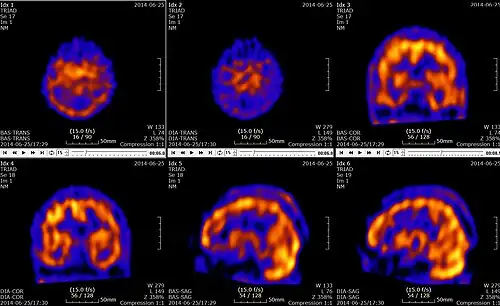

Tomografia emisyjna pojedynczych fotonów, badanie SPECT (od ang. single-photon emission computed tomography) – tomograficzna technika z dziedziny medycyny nuklearnej, która przy użyciu promieniowania gamma umożliwia tworzenie obrazu przestrzennego aktywności biologicznej dowolnego obszaru ciała pacjenta[1].

Radiofarmaceutyk wprowadza się do krwiobiegu w bardzo niskich stężeniach (w zakresie od nano- do pikomolowych)[2] i nakierowuje na określone miejsce. W organizmie ulega on związaniu i przechodząc przemiany nuklearne emituje promieniowanie gamma. Ilość wyemitowanego promieniowania jest zależna od poziomu akumulacji radiofarmaceutyku w danym obszarze. Promieniowanie jest mierzone bezpośrednio za pomocą zewnętrznego detektora – kamery gamma. Do uzyskania projekcji z promieniowania emitowanego z ciała pacjenta nakłada się na detektor kolimator. Jego rolą jest blokowanie fotonów padających pod innym kątem niż prosty. Obraz przestrzenny uzyskuje się poprzez umieszczenie głowicy kamery gamma na mechanicznym wysięgniku, który zapewnia ruch kamery wokół badanego obszaru pacjenta. Zbierane są obrazy z kolejnych położeń głowicy, różniących się o kilka stopni, zwykle 3 do 6. W taki sposób wykonuje się pomiary z pełnego obrotu wokół pacjenta. W zależności od badanego miejsca zabieg trwa od kilku do kilkudziesięciu minut. Proces ten można przyspieszyć poprzez zastosowanie wielogłowicowej gamma kamery. Najczęściej stosuje się kamery dwugłowicowe, umieszczone naprzeciw siebie. Dzięki temu, że mogą one dokonywać pomiarów równocześnie, wystarczy, że wysięgnik dokona tylko połowy obrotu, co przyspiesza dwukrotnie cały proces. Stosuje się również detektory trójgłowicowe obrócone względem siebie o 120 stopni, dodatkowo skracające całe badanie. Wszystkie pozyskane zdjęcia podlegają następnie obróbce komputerowej, która stosując odwrotną transformatę Radona umożliwia stworzenie trójwymiarowego obrazu badanego obszaru. Na podstawie utworzonego obrazu można określić funkcjonalność i metabolizm tego obszaru.

Badania SPECT znalazły szerokie zastosowanie w neurologii. Stosuje się je do badania przepływu mózgowego krwi, guzów mózgu i rozmieszczenia receptorów (opiatowych, benzodiazepinowych, muskarynowych i dopaminowych). Wykorzystuje się do tego dwa radiofarmaceutyki 99mTc-HMPAO i 99mTc-ECD. Pierwszy stosowany jest do badania zmian zachodzących w dużych i średnich naczyniach mózgowych, a drugi do badania przepływu miąższowego.

Jeżeli znacznik w jakimś miejscu nie gromadzi się lub gromadzi w widocznie mniejszym stopniu, oznacza to niedokrwienie ośrodkowego układu nerwowego. Istnieją dwie metody analizy danych uzyskanych w wyniku tego badania. Analiza jakościowa, która polega na ocenie rozmieszczeniu radiofarmaceutyka w tkance mózgu oraz analiza półilościowa, która polega na ocenie międzypółkulowej lub wewnątrzpółkulowej asymetrii perfuzji.

Badania SPECT znajdują zastosowanie również w psychiatrii. Dzięki temu, że umożliwiają badanie funkcji mózgowych poprzez przepływ mózgowy krwi, można wykryć wiele zaburzeń psychicznych. Zdjęcia uzyskane w ramach tego badania w ramach analizy porównuje się z obrazami przedstawiającymi znane przypadki chorób i zaburzeń, co pozwala na dostrzeżenie podobieństw zachodzących procesów biologicznych. W ten sposób można wykryć zaburzenia już we wczesnych fazach ich występowania.